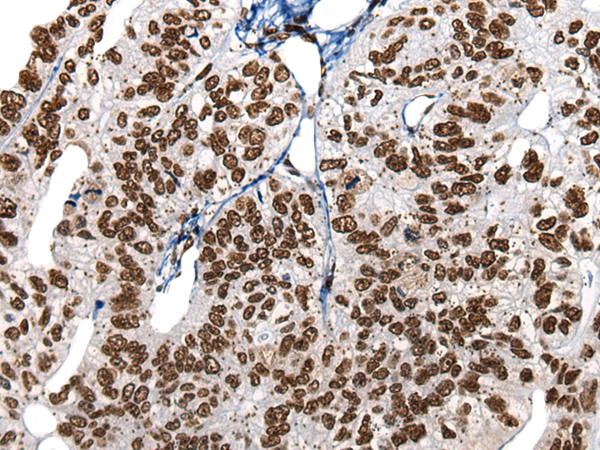

![HNRNPR Antibody[46577]](https://img1.dxycdn.com/p/s14/2025/0923/615/4857477420976040791.jpg)

The image on the left is immunohistochemistry of paraffin-embedded Human gastric cancer tissue using 46577(HNRNPR Antibody) at dilution 1/20, on the right is treated with synthetic peptide. (Original magnification: x200)

![HNRNPR Antibody[46577]](https://img1.dxycdn.com/p/s14/2025/0923/813/6144446710976040791.jpg)

The image on the left is immunohistochemistry of paraffin-embedded Human liver cancer tissue using 46577(HNRNPR Antibody) at dilution 1/20, on the right is treated with synthetic peptide. (Original magnification: x200)